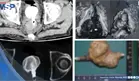

Hematuria reveló adenocarcinoma mucinoso de células en anillo de vejiga con metástasis pulmonar y ósea